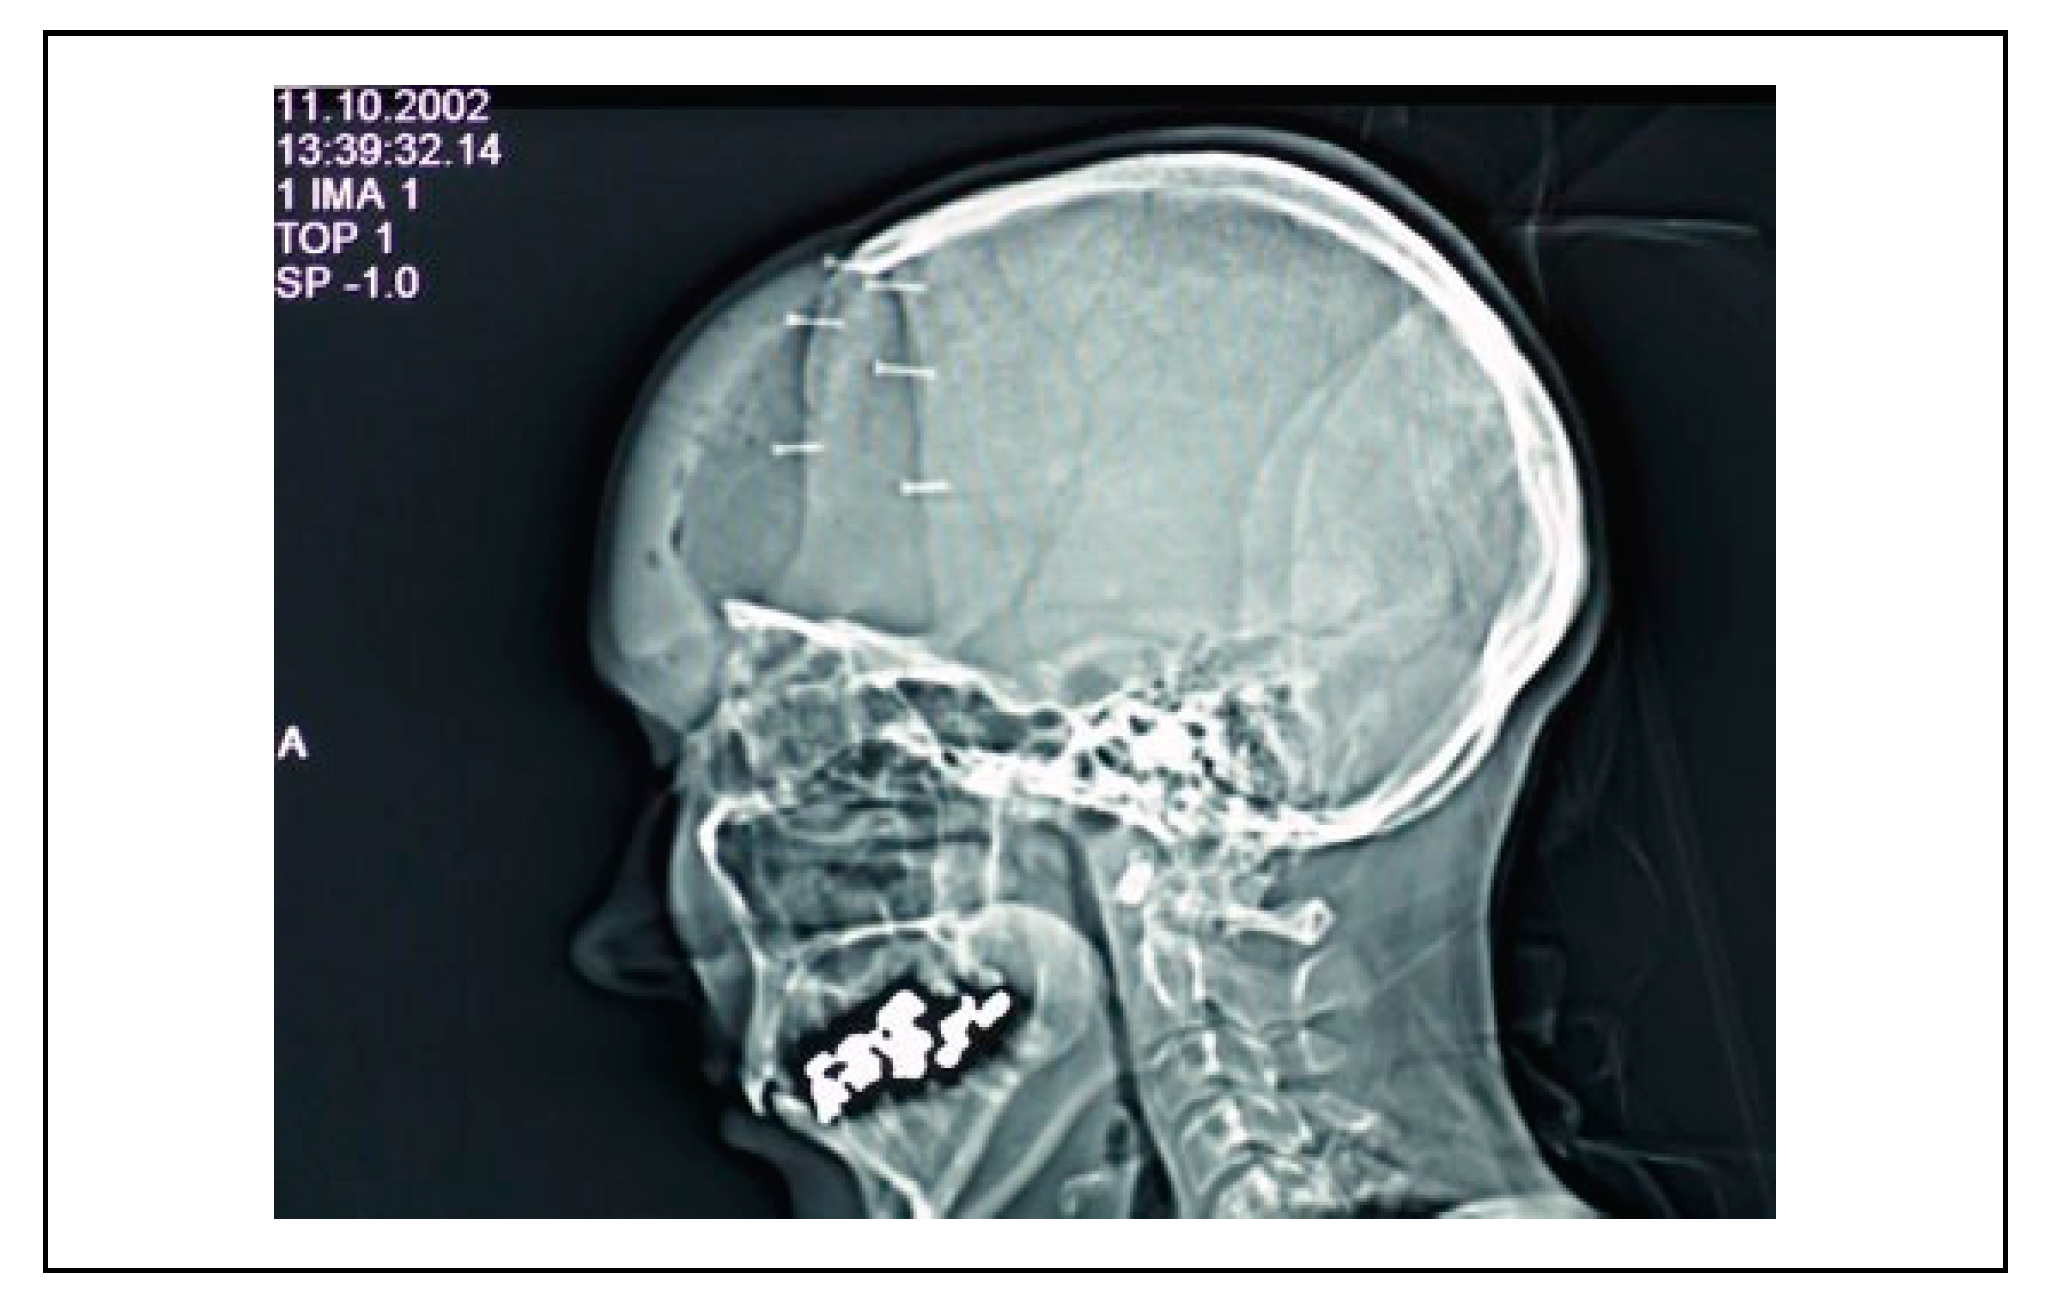

Ceramic 3D-Printed Titanium Cranioplasty

Case Material

Results